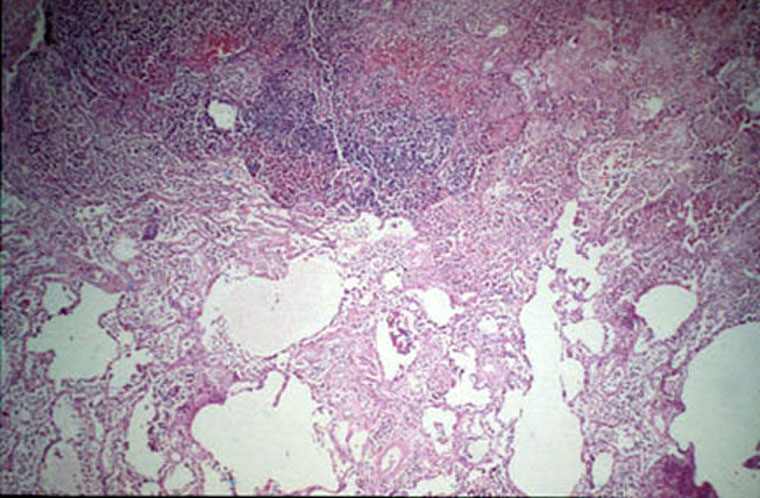

Staph aureus/Pneumonia. (Dr Aliya Husain)

Lung abscess /gross.  (Dr Ralph Leischner)

Lung abscess/ gross.  (Dr Ralph Leischner)